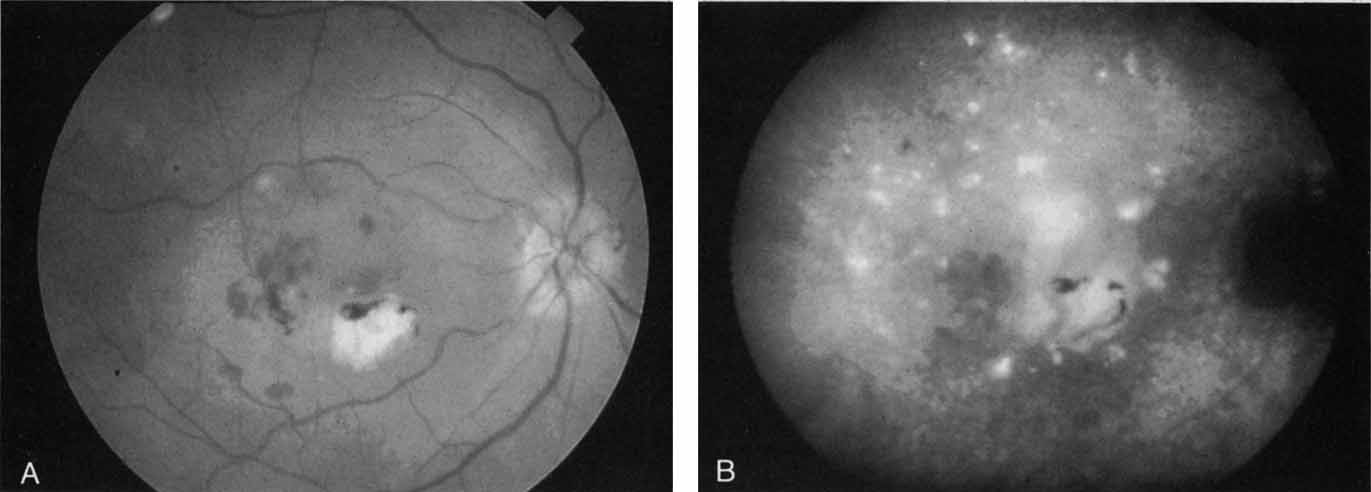

An important report by Chang and co-workers27 lends support to the rationale for interpreting the hyperfluorescence seen on ICG angiography as CNV. In this clinicopathologic study, a patient was identified who had experienced subretinal hemorrhage with early signs of occult CNV on fluorescein angiography (Fig. 4A). Fluorescein angiography demonstrated blocked fluorescence (Fig. 4B). The ICG study, however, demonstrated late staining in a well-circumscribed fashion, which the authors interpreted as a “plaque” of occult CNV (Fig. 4C). When the patient died, this area was evaluated and studied histopathologically and compared with the picture seen on ICG angiography. The area of hyperfluorescence on the ICG study corresponded precisely to a thin layer of fibrovascular tissue beneath the pigment epithelium and neurosensory retina, confirming that the late-staining tissue imaged with ICG angiography was truly a neovascular membrane (Fig. 4D).